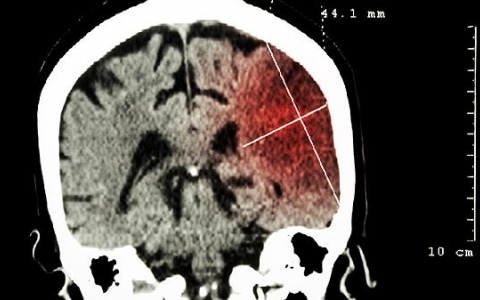

脑溢血的前兆是什么?

脑溢血是日常生活中比较常见的一种疾病,好发于老年人群居多,一般发病时间为冬季较多,出现脑溢血十分危害身体健康,甚至是危害到生命危险,而出现脑溢血会容易出现一些前